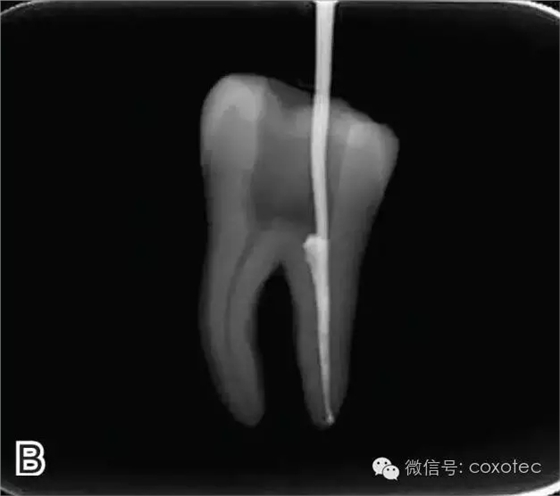

圖2 選擇垂直加壓器,A.試垂直加壓器 B.垂直加壓器在根內的位置 選擇非標準牙膠尖(如0.04、0.06 錐度牙膠尖)作為主尖,型號一般與根管預備最大號的器械型號一致,能到達距根尖0.5~1 mm 處,主尖尖段與根管壁緊密接觸。拍試尖X 線片進行確認(圖3)。

圖3 試尖,A.試主尖 B.拍試尖X片